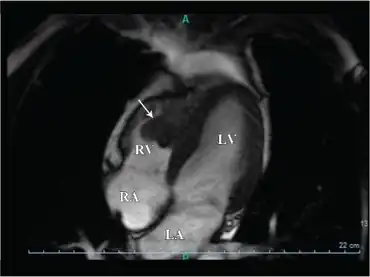

Lobulated mass lesion arrow in right ventricle

The excessive clotting that occurs in this disorder is almost always restricted to the veins,[13] where the clotting may cause a deep vein thrombosis (DVT). If the venous clots break off, these clots can travel through the right side of the heart to the lung where they block a pulmonary blood vessel and cause a pulmonary embolism. It is extremely rare for this disorder to cause the formation of clots in arteries that can lead to stroke or heart attack, though a "mini-stroke", known as a transient ischemic attack, is more common. Given that this disease displays incomplete dominance, those who are homozygous for the mutated allele are at a heightened risk for the events detailed above versus those who are heterozygous for the mutation.[14]